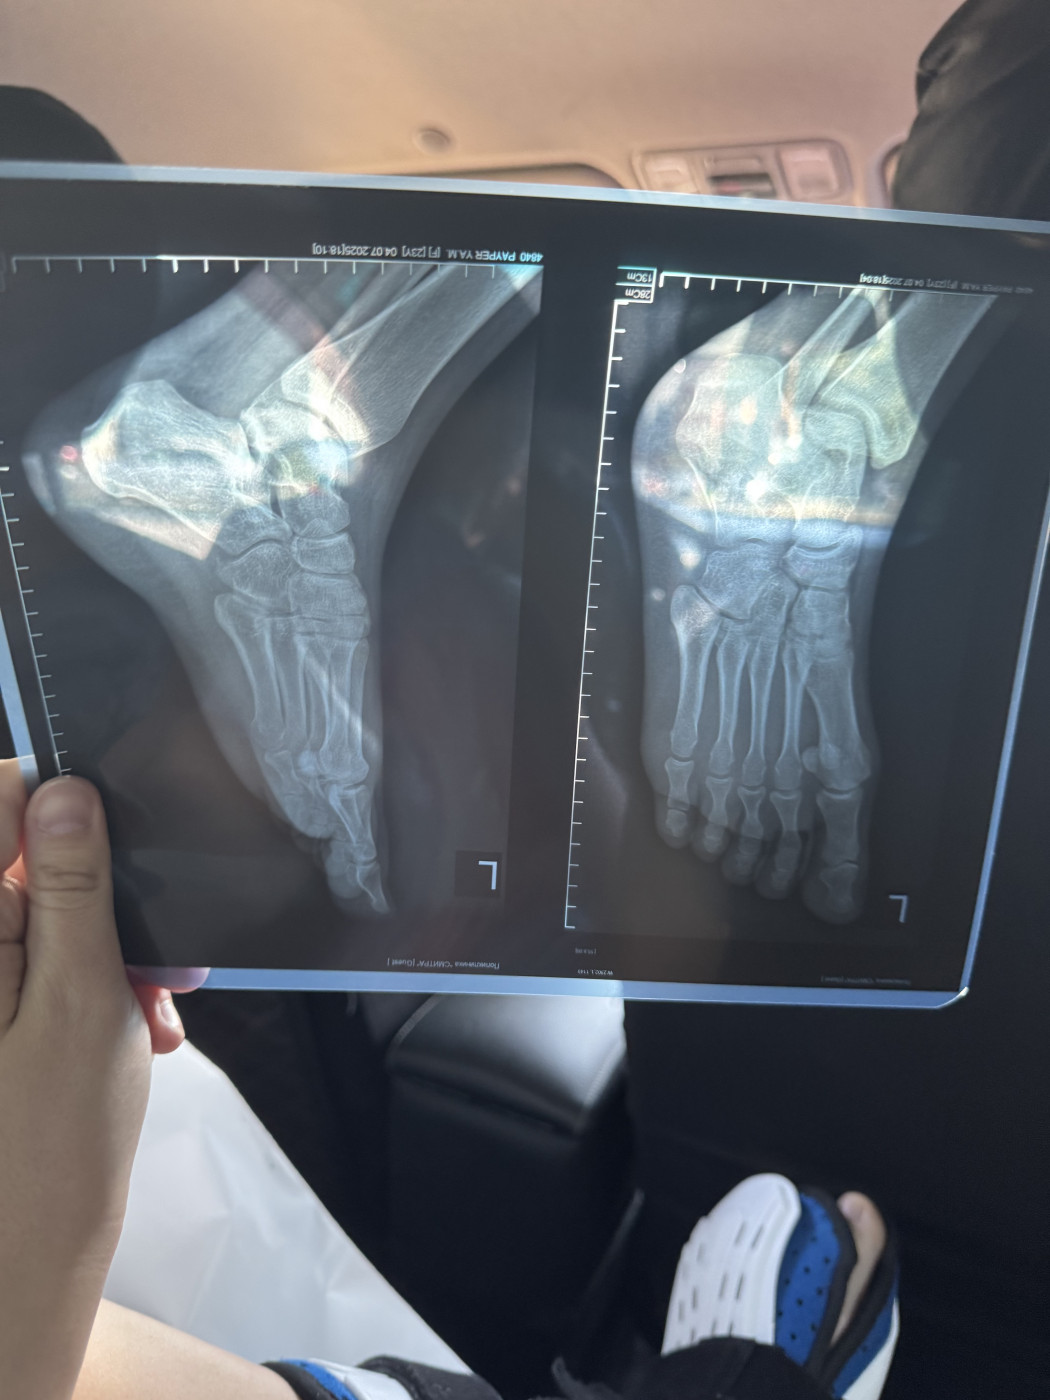

Жмет пластиковый ортезДобрый день! 3 ноября я сломала пятую плюсневую кость на левой ноге, перелом без смещения. Мне наложили гипс. 15 ноября после повторного рентгена (снимок от 15 ноября на фото) мне наложили пластиковый ортез ordect и сказали, что я могу ходить с опорой на пятку. Но этот ортез мне жмет, мизинец очень плотно прижат к другим пальцам. |